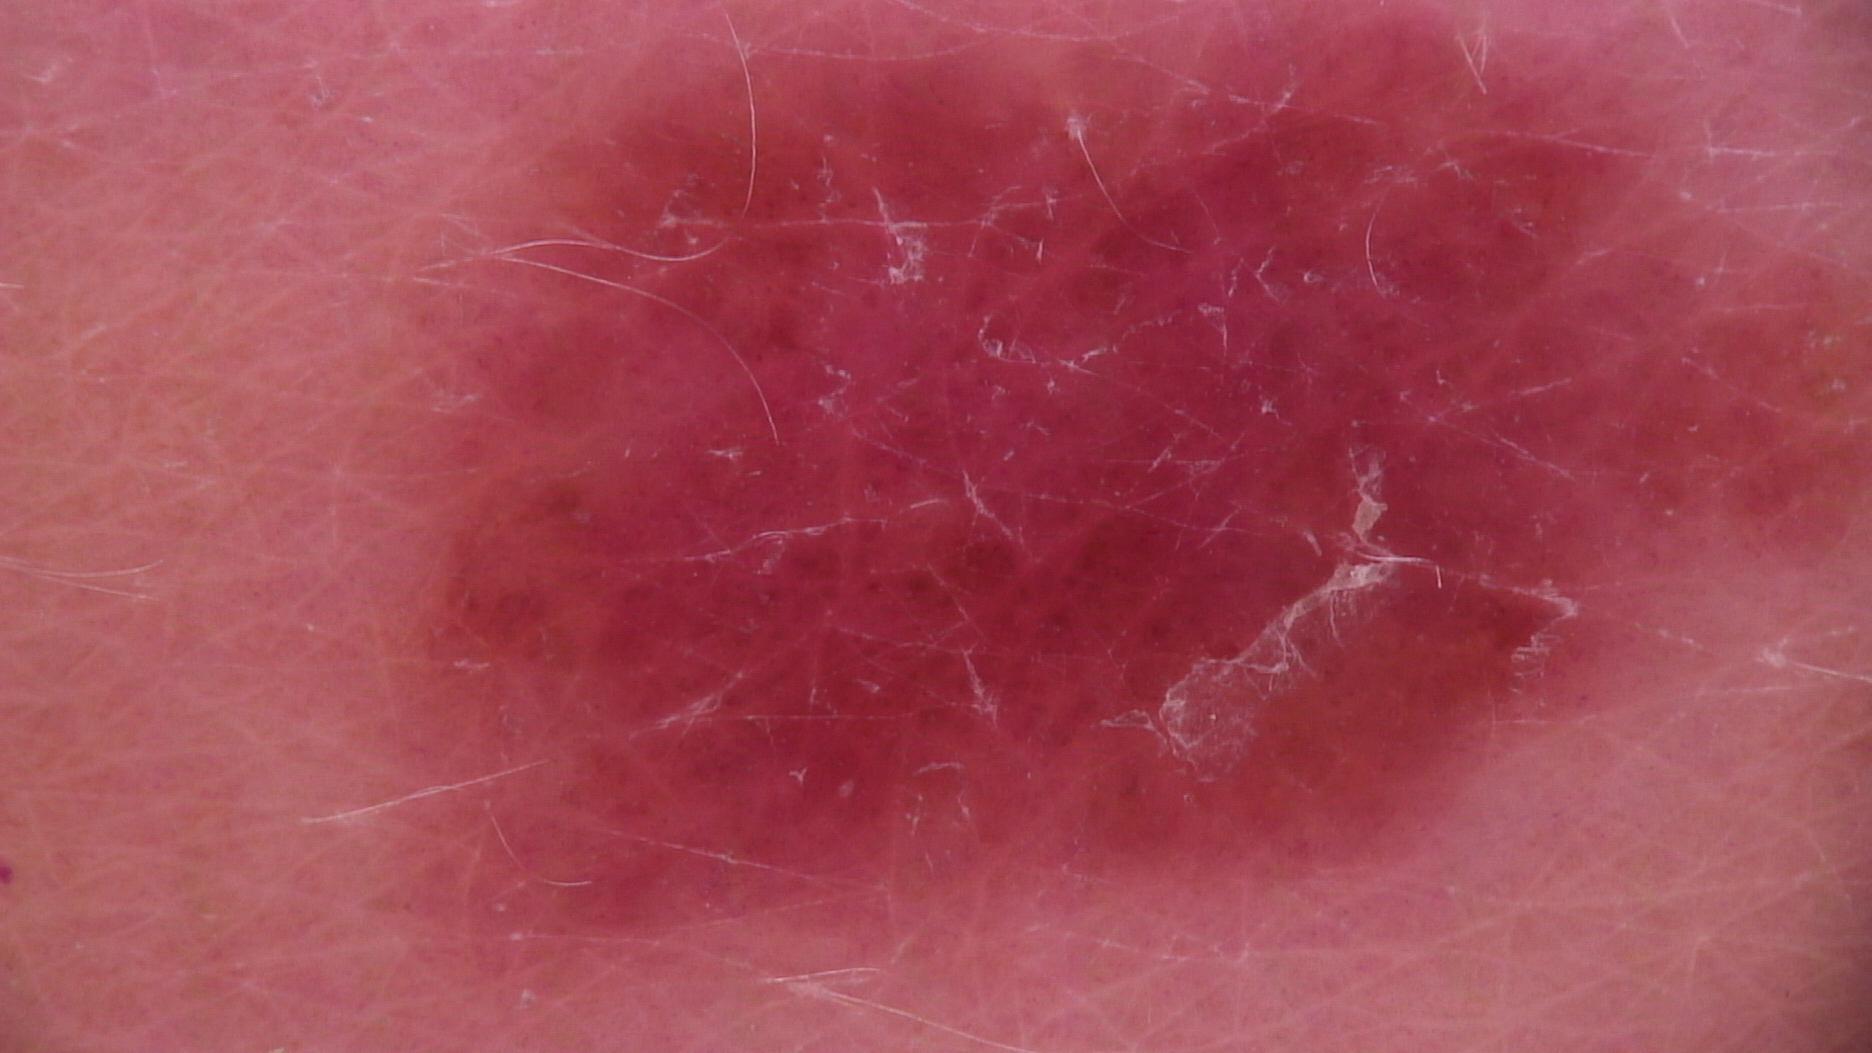

age_approx 45

concomitant_biopsy False

dermoscopic_type contact polarized

diagnosis_1 Benign

diagnosis_2 Benign melanocytic proliferations

diagnosis_3 Nevus

diagnosis_confirm_type serial imaging showing no change

image_type dermoscopic

melanocytic True

sex female